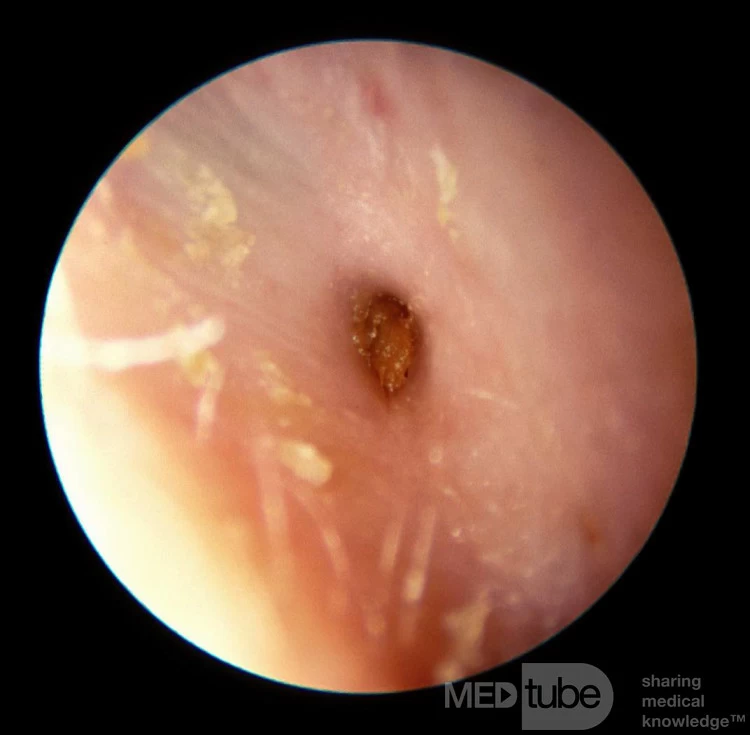

otomycosis

fungal infection

itching, burning, pain, discharge, hearing loss

Skin conditions and humid environment

Treatment: prescribed ear dropsa